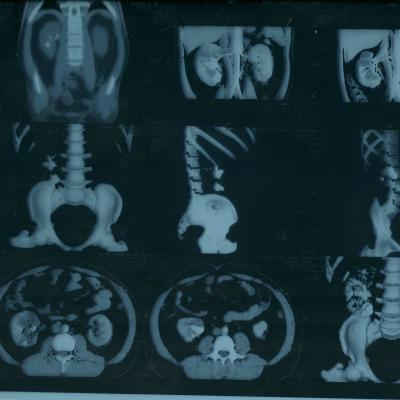

коралловидный камень

Морозов Алексей. Здравствуйте,находился

на лечении в урологическом отделении

г.Йошкар-Ола по поводу МКБ, В правой почке

обнаружен коралловидный камень,врач

рекомендовал ЧПНЛ в Нижнем Новгороде,но